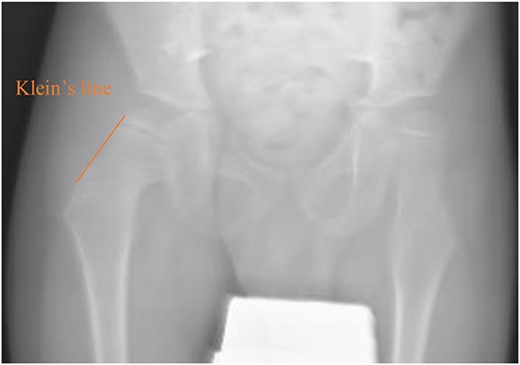

A 5-year-old independent ambulatory Middle Eastern boy with CP who was born preterm and developed grade III intraventricular haemorrhage and periventricular leucomalacia and was on AEDs, including valproic acid (VPA) and levetiracetam (LEV), for >3 years and was controlled over the last year (no history of seizure attack) presented to the emergency room (ER) with right hip pain and inability to bear weight for 4 weeks; the patient had no history of fever or trauma. Physical examination shows a thin, the weight is 12 kg, the height is 101 cm, vital signs within the normal range, tenderness over the right hip, and external rotation of the right hip, with restricted hip mobility. A radiological study was performed ~3 months before the patient presented to the ER for follow-up examination of a left hip coxa valgus deformity with no apparent abnormalities in the right hip (Fig. 1). Initial imaging studies conducted in the ER showed an anterior–posterior view of the pelvic radiograph, revealing Klein’s line [13] not intersecting the capital femoral epiphysis (Fig. 2), and frog-leg lateral view radiograph of the right hip (Fig. 3) confirmed SCFE and Southwick’s slip angle [13] of ~50° (moderate). Laboratory findings were clear for endocrine and renal diseases or infection, except for low vitamin D (total 25-OH Vitamin D: 43.4 nmol/L), suggesting vitamin D insufficiency. The diagnosis was confirmed with clinical and radiological studies as right-sided unstable SCFE requiring surgery. Surgical intervention was performed with percutaneous in situ fixation using a single fully threaded 4.5-mm cannulated screw (Fig. 4). Postsurgical rehabilitation included non-weight-bearing right lower extremities for 6 weeks. Regular follow-up with serial radiology studies showed stable fixation with no migration of screw or further slippage at 6 weeks (Fig. 5) and 3 (Fig. 6), 15 (Fig. 7), and 36 months (Fig. 8). During follow-up, a painless range of motion in the right hip was observed, with full weight-bearing and resumption of his usual activities with no complaints.

Pelvic anterior–posterior radiograph showing SCFE in the right hip, with Klein’s line not intersecting the capital femoral epiphysis